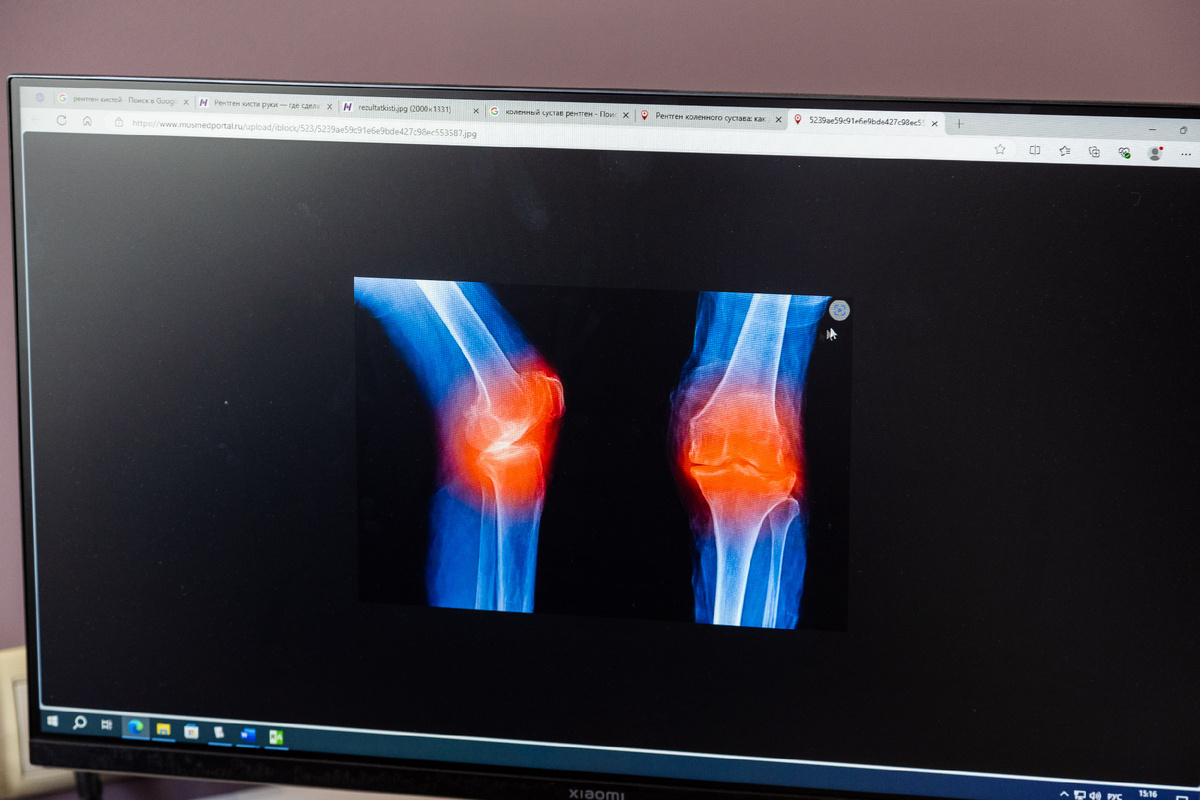

Когда обратить повышенное внимание на отёк колена?

Продолжая бездонную тему про колени, сегодня предлагаю поговорить про отёки. Когда следует обратить повышенное внимание на проблему ❶ когда уже есть боли в коленном суставе. Они могут быть «стартовыми» после сна, либо после долгого сидения на работе, либо, напротив, после продолжительного «стояния» на ногах. ❷ когда идёт увеличение отёка. В этом случае нормальная работа коленного сустава затруднена, нередко человек большую часть нагрузки при ходьбе переносит на здоровую ногу. ❸ когда наблюдается повышение температуры в области отёка ❹ когда сустав увеличивается в размерах  ❺ когда вместе с отёком колена идёт общее повышение температуры тела. Если что-то из перечисленного, вы уже наблюдаете у себя, то не поленитесь обратиться к врачу. Проблема может оказаться серьёзнее, чем вы думаете. На приём с вышеуказанными жалобами можно записаться к ортопеду или ревматологу.  В следующий раз подробнее остановимся на травматическом и нетравматическом характере болей в коленях. Рассмотрим, к